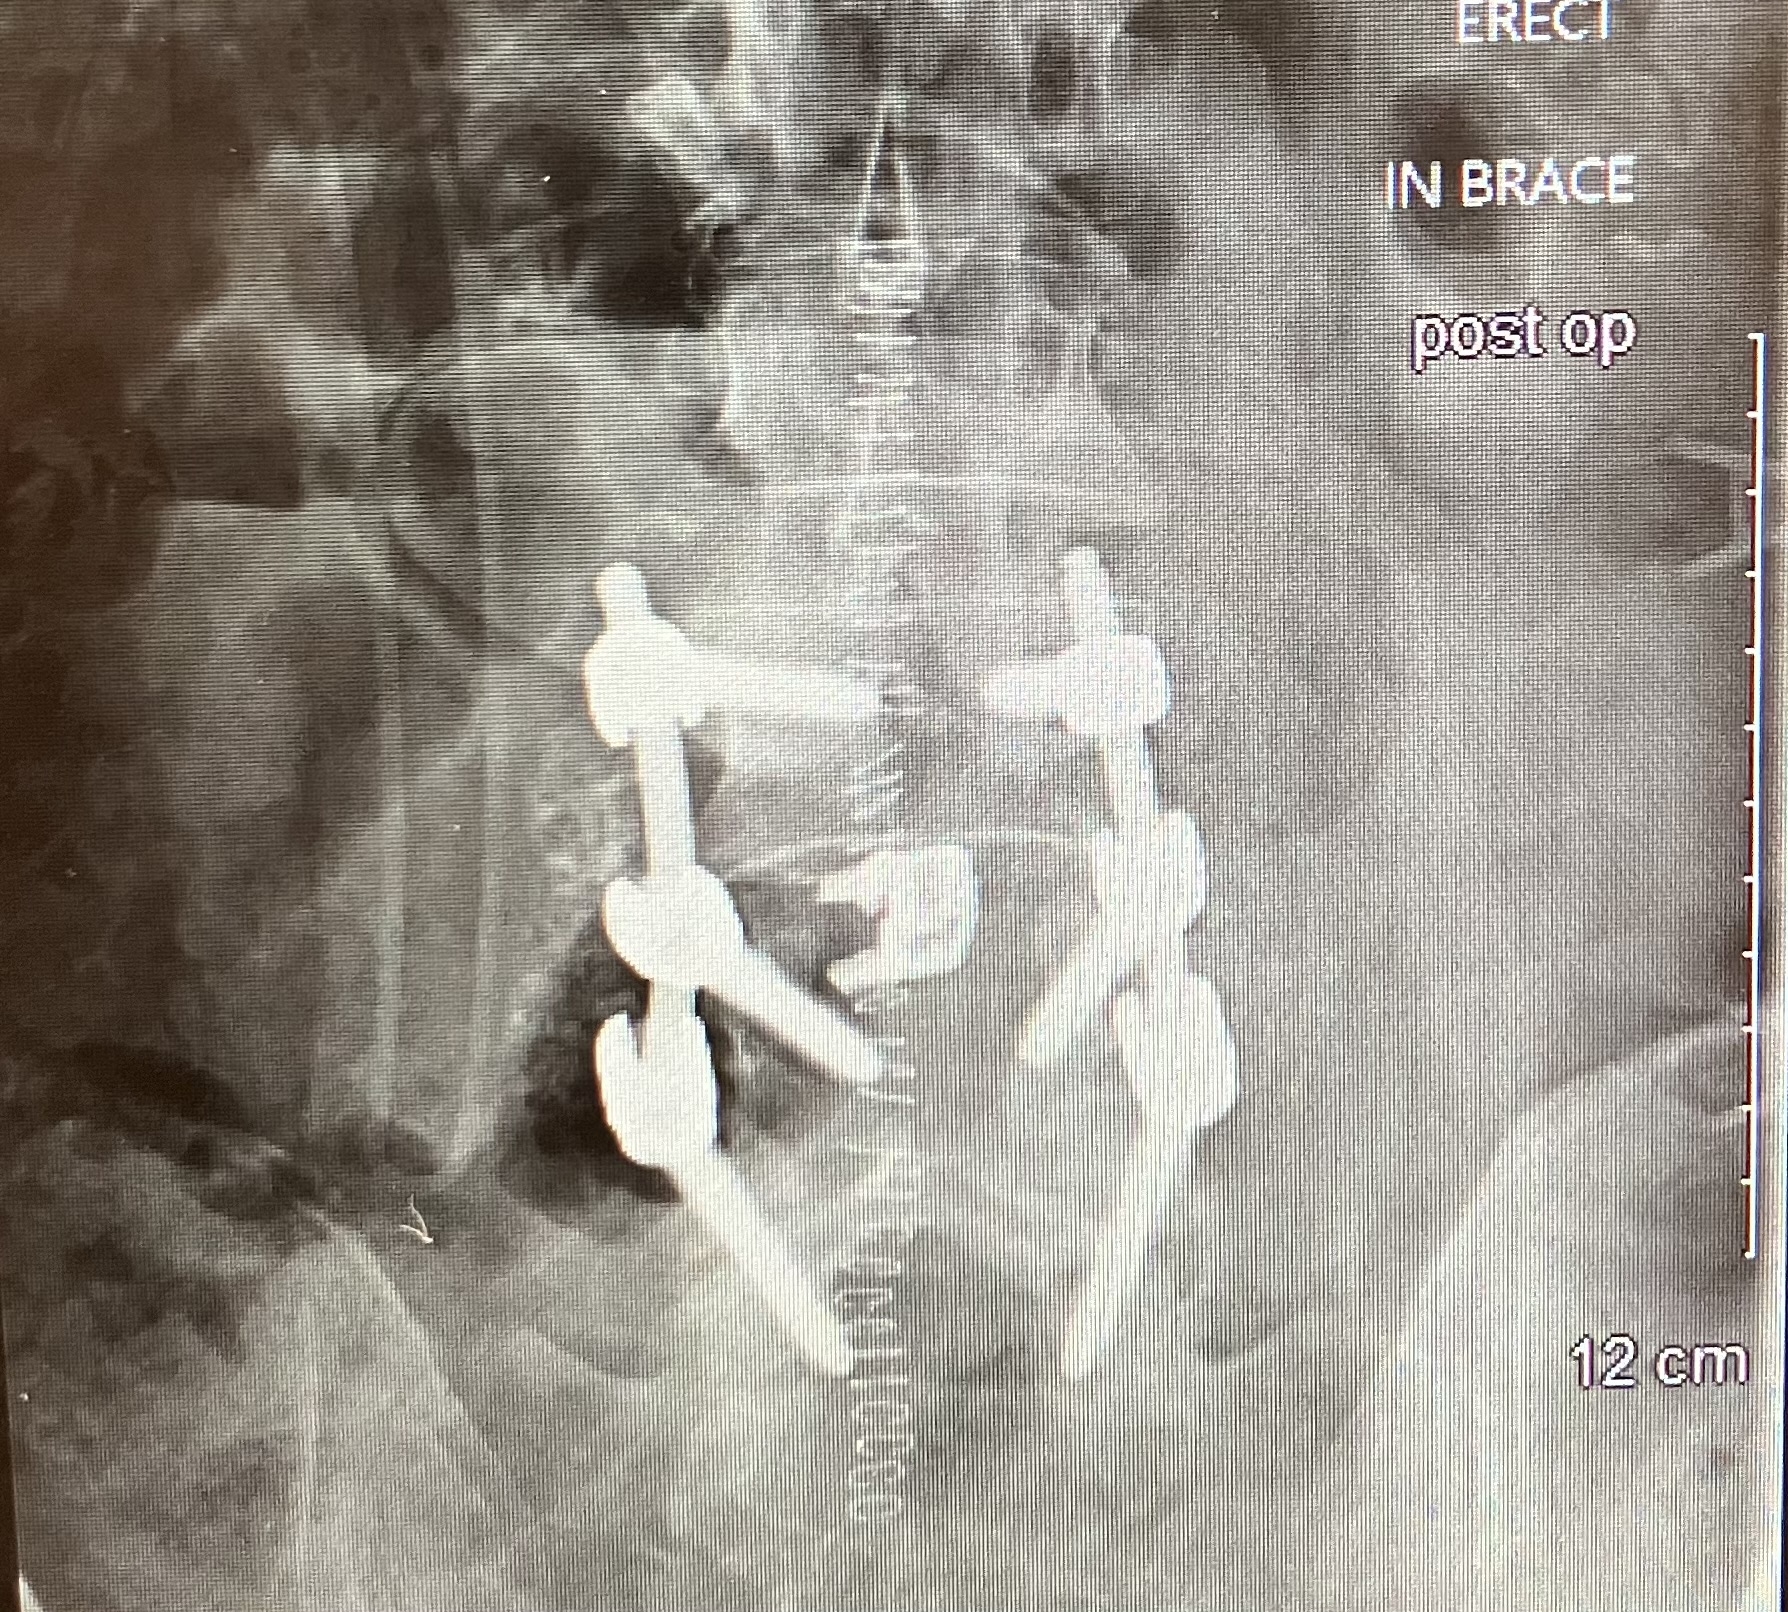

Spinal decompression and fusion surgery. Woo hoo! ;)

Finally got some pictures.... 6 bolts, two rods, a spacer, some self dissolving suture, 41 staples, a walker (tennis balls on the rear legs, of course), a slide in bathtub shower seat, a toilet seat extender, a bone growth stimulator, and a bunch of comfy sweat pants. 😂

I can hear the buzzer at airport security already....